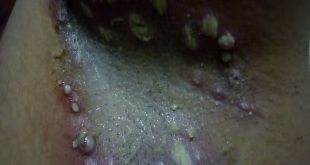

Ce patient consulte pour une érythrodermie sèche d’installation récente, l’examen confirme l’érythrodermie et retrouve en …

C ‘est beaucoup plus profond !